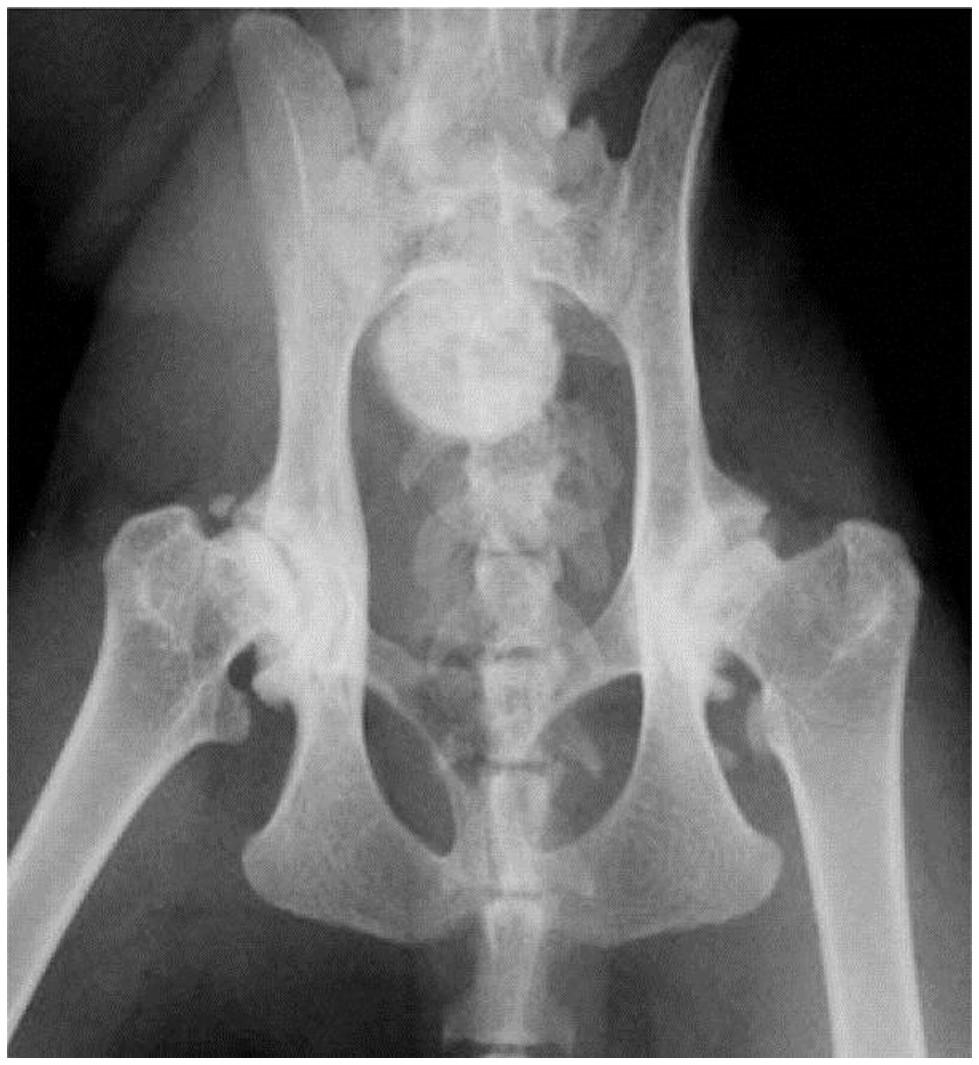

From www.mdpi.com

Animals Free FullText Knee Joint Osteoarthritis in Overweight Cats Cat Osteoarthritis Treatment Uk A 10% reduction in body weight helps alleviate joint strain. There are many aspects to successfully treating arthritis. Since arthritis is a progressive disease, it will unfortunately get worse over time. treatment of arthritis in cats. As a progressive disease, it can. the decision to treat cats with ckd and oa must be based on a thorough discussion. Cat Osteoarthritis Treatment Uk.